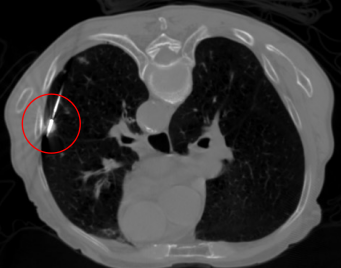

考虑到患者情况,我院呼吸与危重症医学科王开金副主任组织肺结节与肺癌MDT讨论,征得患者及家属同意后,决定为患者实施微波消融术。1月9日由王开金副主任带领的呼吸介入团队,在CT引导下为患者行局麻下肺结节微波消融术。手术顺利,术中患者无不适,术后恢复良好。

微波消融术中